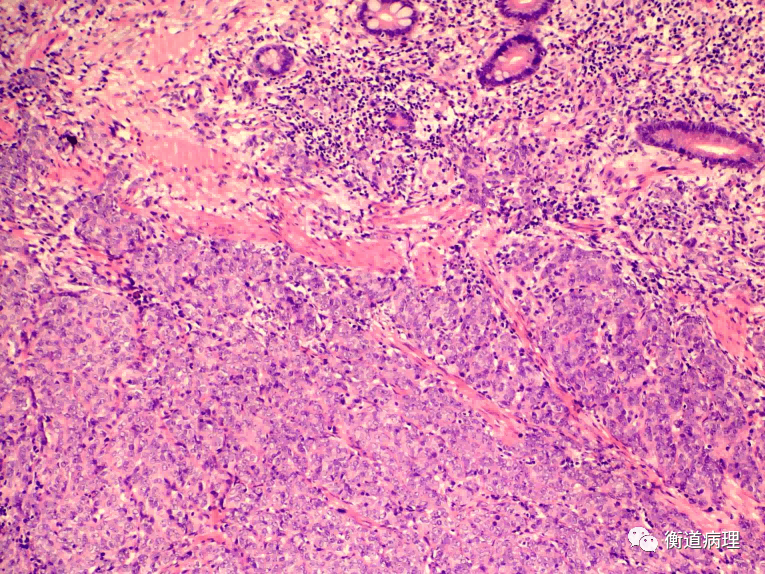

【衡道丨笔记】「三甲病理现场」课程学习笔记(十八):恶性黑色素瘤的

图片尺寸1080x961